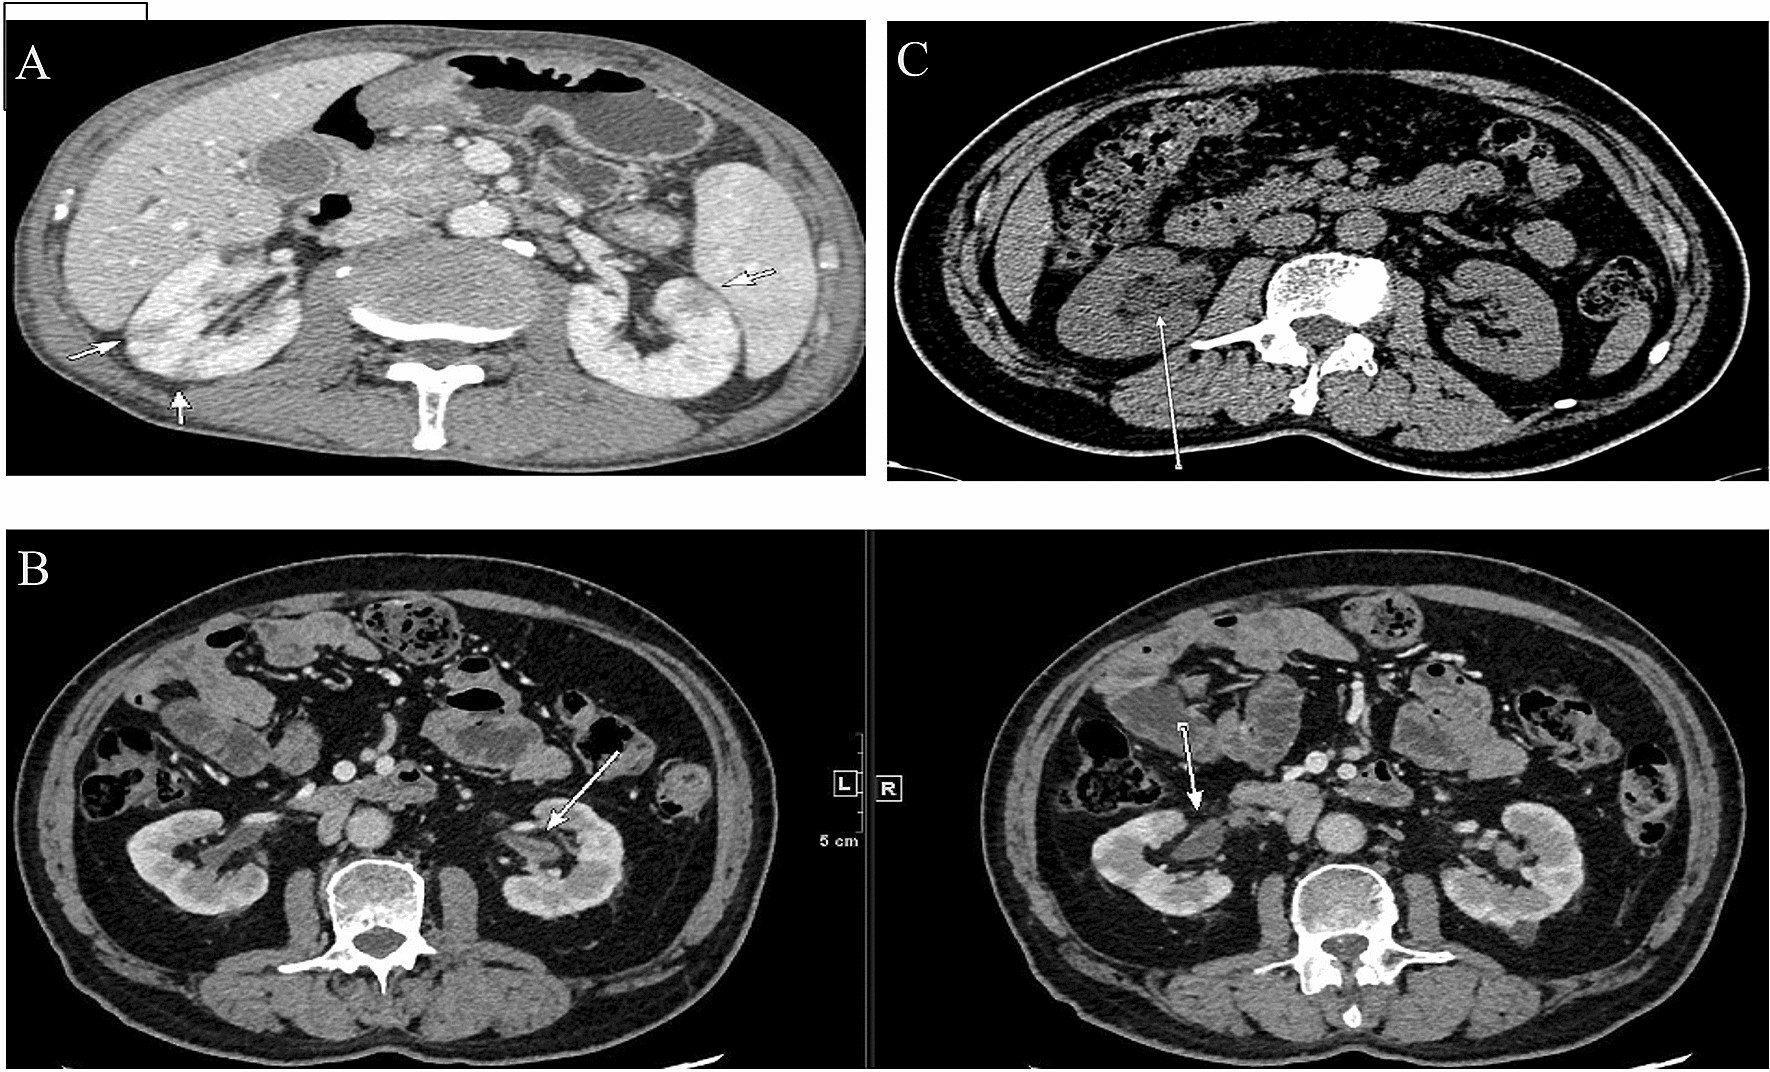

Figure 4

Representative contrast-enhanced CT imaging of IgG4-RKD+ . (A) Multiple low-density lesions in the bilateral kidneys (arrows). (B) ureteric obstruction and hydronephrosis related to RPF (arrow). (C) Renal pelvis thickening with smooth intraluminal surface (arrows).